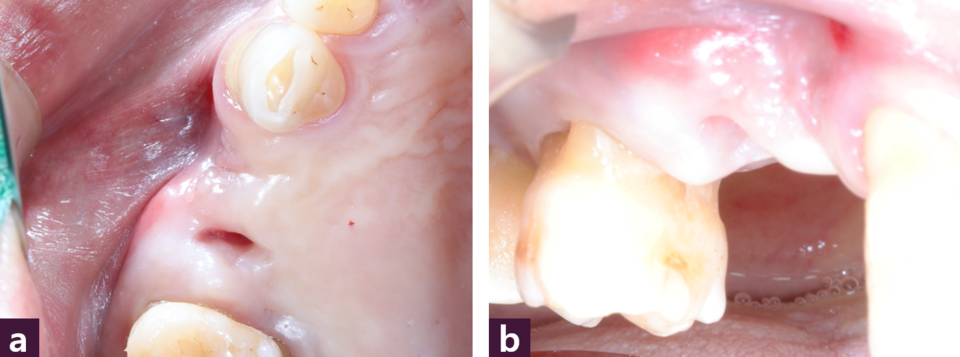

구강내 소견으로 #14 부위 협측 치은이 함몰된 양상을 보이고 있다 [그림 4].

MagiCore 임플란트 식립 후 구강 내 사진에서 협측 함몰부가 골이식과 임플란트의 식립으로 인접치은과 비슷하게 개선된 모습을 볼 수 있다 [그림 6].